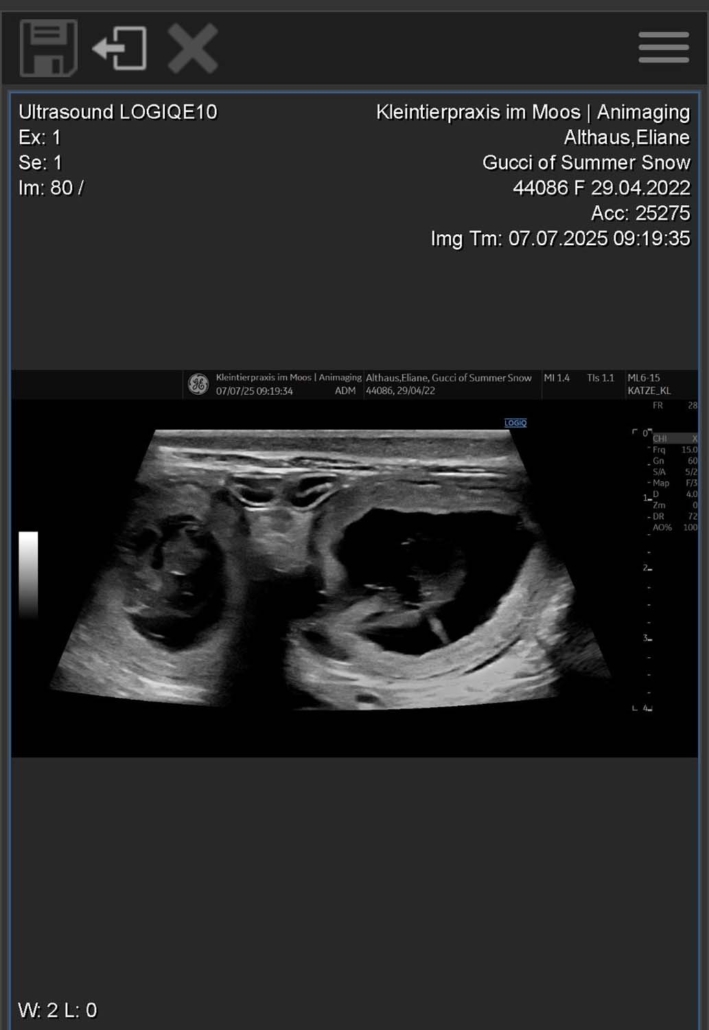

Gucci of Summer Snow | Geboren am 29.04.2022

Gucci ist trächtig – und wir freuen uns riesig auf Mitte August! Auf dem Röntgenbild sind vier kleine Parson Russell Terrier-Welpen zu erkennen! 🐶🐶🐶🐶